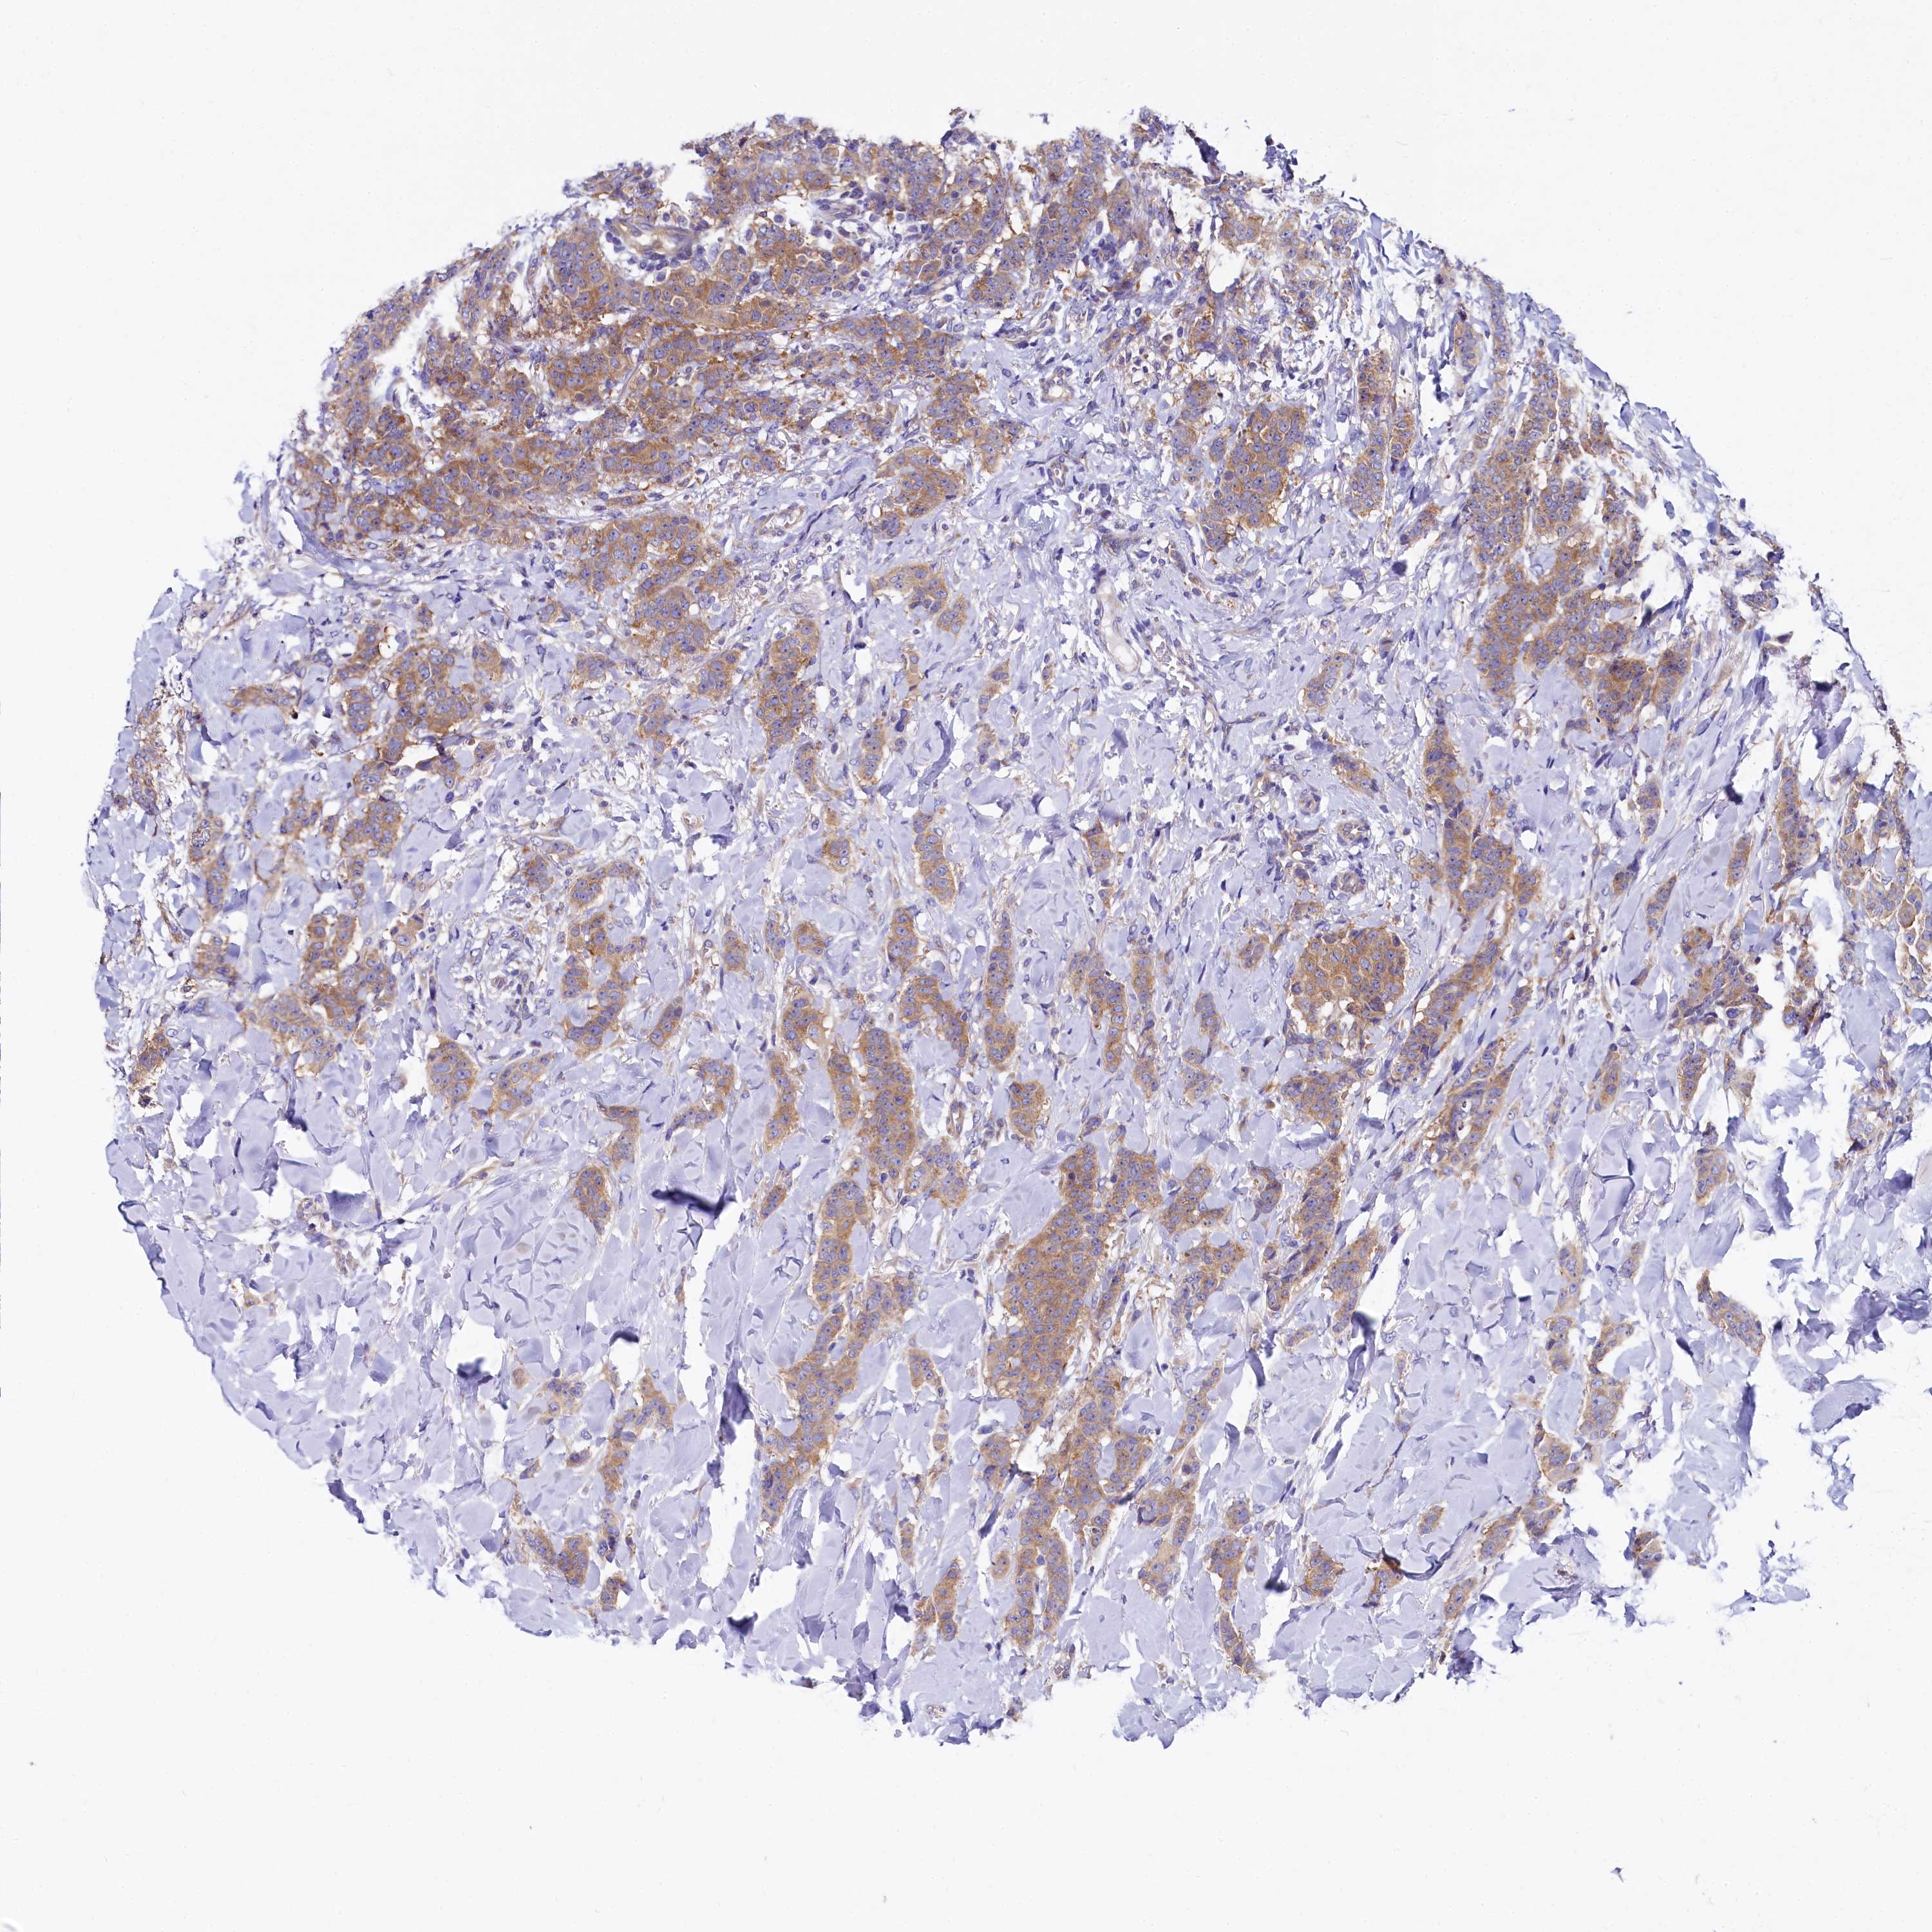

CANCER BREAST CANCER Show tissue menu

BRCA TCGA BRCA VALIDATION PROTEIN EXPRESSION